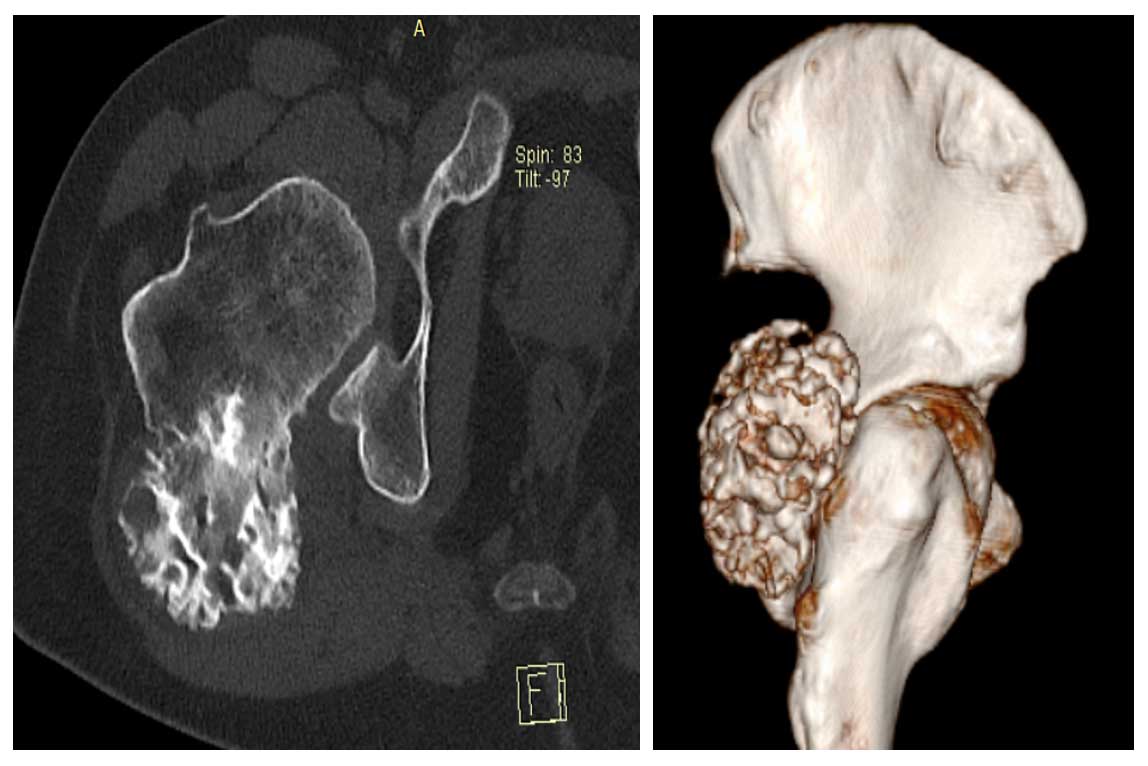

Ameliyat Öncesi: Tomografide proksimal femur posterior kaynaklı düzensiz sınırlı tümör dokusu görülmekte.